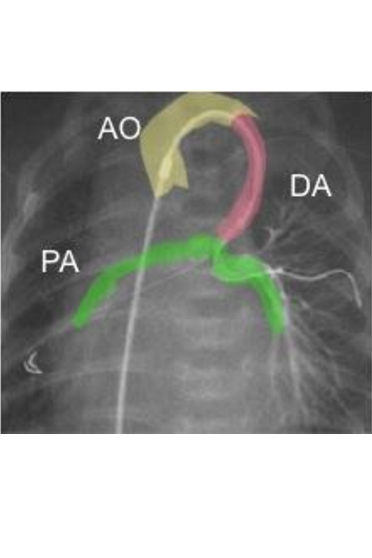

Visualisation of the ductus arteriosus in a pulmonary atresia

The blood flows from the aorta (yellow) via the ductus (pink) into the pulmonary artery (green). There is no pulmonary valve here and the ductus is the only blood supply for the pulmonary artery (AO = aorta, DA = ductus arteriosus, PA = pulmonary arteries).